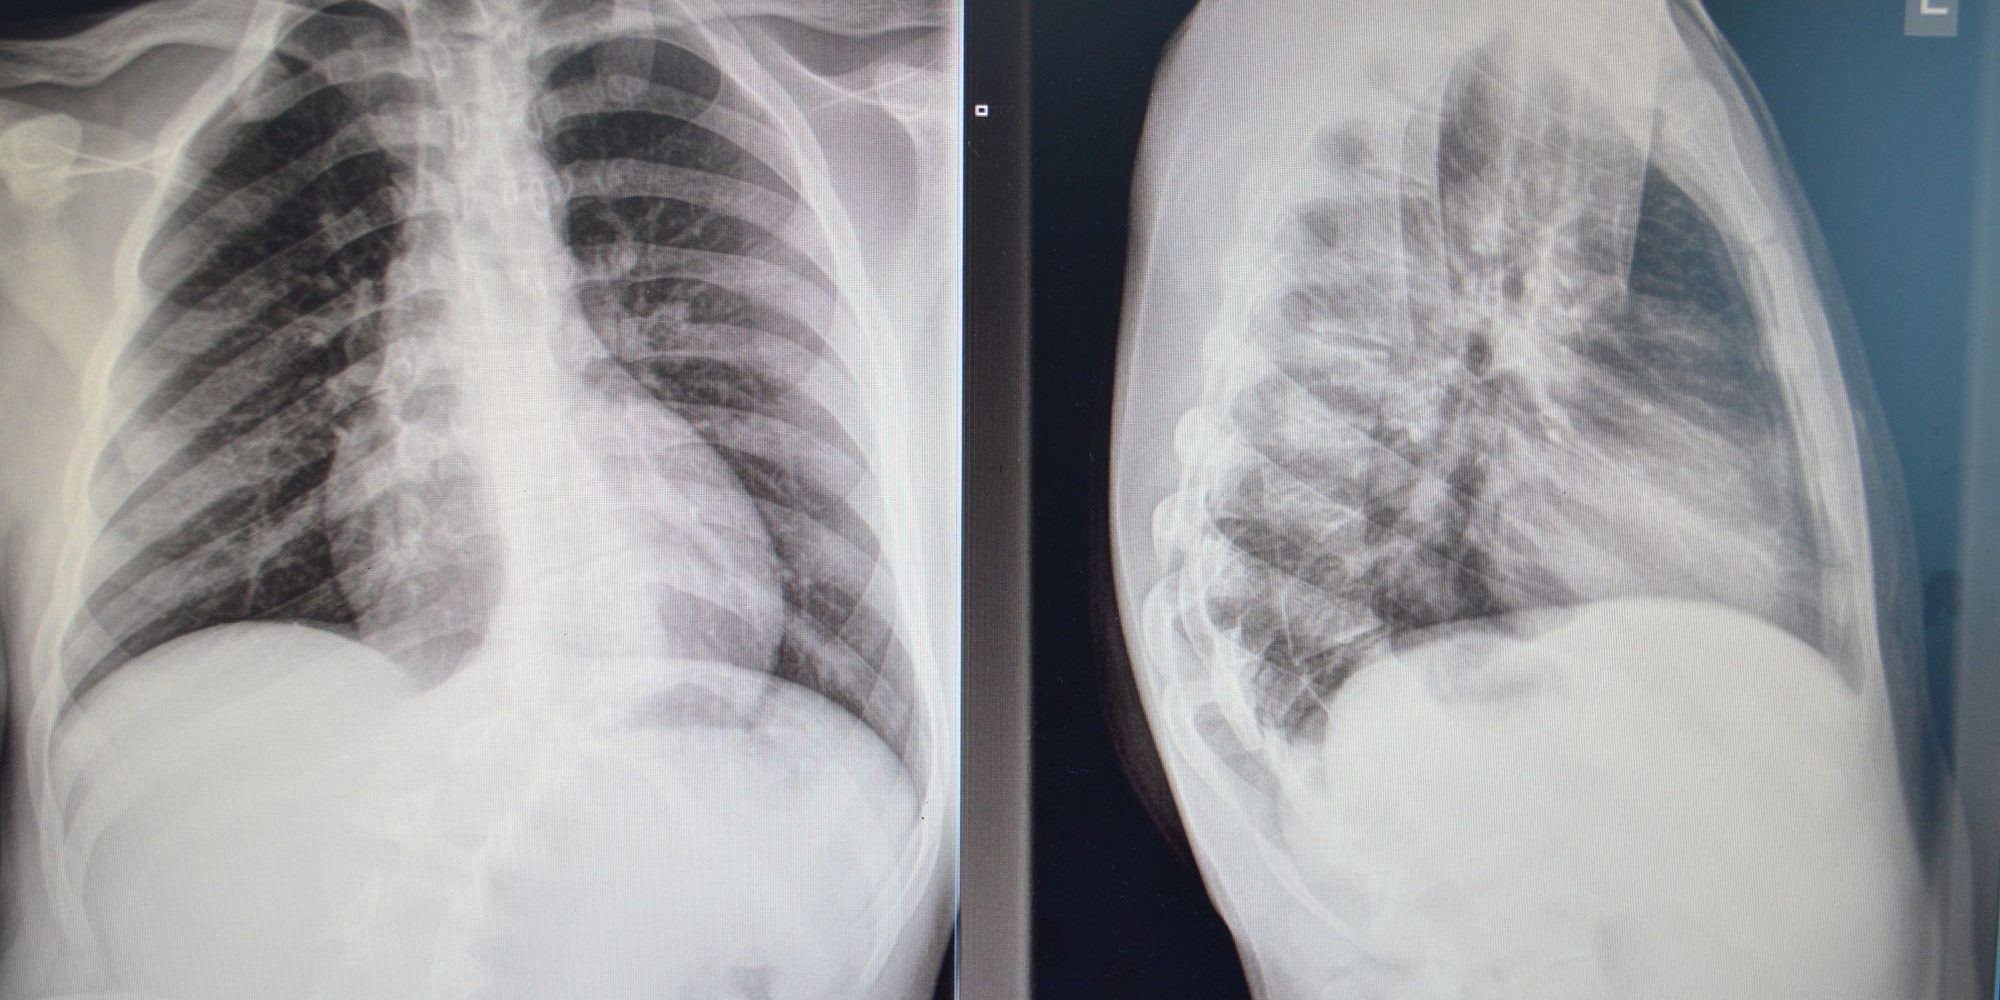

Prema riječima v. d. načelnika Klinike za ortopediju i traumatologiju UKC Tuzla, doc. dr. Aleksandra Vujadinovića, kod šesnaestogodišnjeg pacijenta iz Konjica urađena je ekscizija hemivertebrae prilikom koje je uklonjen abnormalano oblikovani pršljen kičmenog stuba. Kako je istakao doc. dr. Vujadinović radi se o operaciji kongenitalne skolioze, odnosno urođene skolioze koja nastaje zbog poremećaja u razvoju određenog dijela kičmenog stuba, konkretno pršljena. “Poremećaj se javlja u periodu od 4. do 6. nedjelje intrauteriog razvoja, ne može se predvidjeti, niti spriječiti. Vremenom kako organizam raste i kako se kičmeni stub izdužuje tako se i deformitet povećava. Mi smo po prvi put uradili operativni zahvat koji se sastoji od isjecanja i odstranjenja tog pršljena na način da usput izvršimo i korigovanje skolioze, koliko je to moguće u ovoj životnoj dobi, i tako spriječimo dalji nastanak deformiteta. Ova operacija je bila visokog rizika zbog mogućih neuroloških ispada, pa i oduzetosti donjih ekstremiteta, te smo prije operacije pacijenta i njegove roditelje upoznali sa mogućim rizicima. Operacija i postoperativni tok su protekli uredno i zadovoljni smo ishodom”, rekao je doc. dr. Vujadinović.